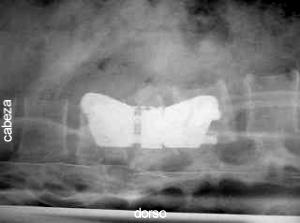

Fotografía A:

Ubicación e identificación de la lesión vertebral por fluoroscopia per operatoria. paciente en decúbito supino. (imagen de control)